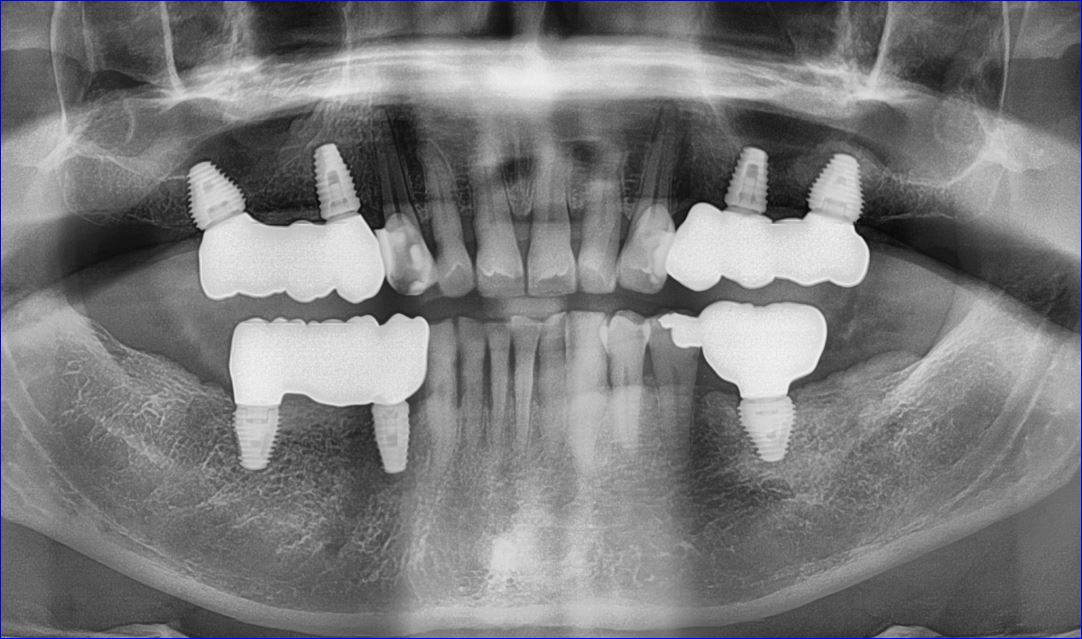

SIMULTANEOUS REHABILITATION OF ALL BACK TEETH

55 years old male had lost posterior teeth in all 4 quadrants, had collapsed bite with moderate TMJ arthrosis.

Dr. Andrews performed a SINGLE surgery – 7 implants placed along with few extractions and bi-lateral crestal sinus lifts.

Restored 100% digitally, utilizing CAD-CAM technologies, all screw-retained full contour zirconia implant crowns with life-time warranty for breaking/chipping.

Collapsed bite had been opened with Gneuromuscular technique. Occlusion was equilibrated 2 weeks after delivery with TENS. Cavities on front teeth were filled with tooth-colored composite fillings.